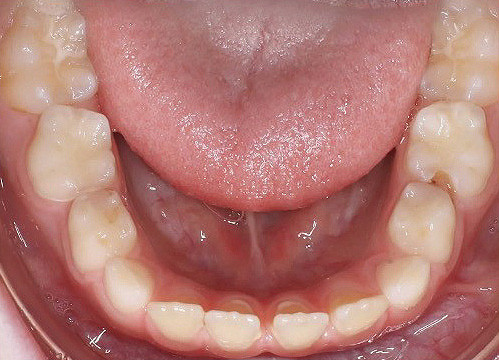

Klinisches Fallbeispiel 2 (Abb. 2a–y)

Distalbiss und tiefer Biss bei einem zwölfjährigen Mädchen. Die Behandlung erfolgte mit Invisalign und Precision Wings. Insgesamt waren zwei Schienensätze notwendig. Die Gesamtbehandlung dauerte 18 Monate.Bei der Planung des ClinCheck wurde der tiefe Biss vorwiegend über eine Intrusion der Unterkieferfront behoben, um die Lachlinie der Patientin nicht negativ zu beeinflussen. Die Oberkieferfront wurde nur retrudiert, jedoch vertikal nicht intrudiert. Während der Phase des Mandibular Advancement wurde die Wirkung der Precision Wings durch den Einsatz von Klasse II-Gummizügen unterstützt. Schlussendlich wurde auch der hängenden Okklusionsebene durch eine einseitige Intrusion der Molaren im ersten Quadranten Rechnung getragen.